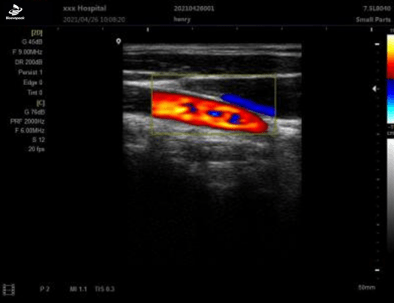

PW模式

| 显示模式 | B、 B/B、4B、B+M、CFM、B+CFM、PDI、B+PDI、PW |

| 应用方式 | 妇产科、小器官、泌尿科、儿科、心脏等 |